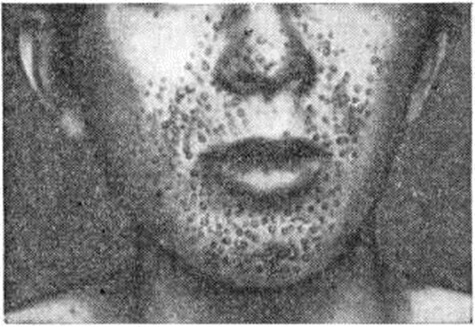

Рис. 4. | ||

Клиническая картина. Заболевание развивается у детей 1—3 лет, начинается обычно с возникновения эпилептических припадков (смотри полный свод знаний: Эпилепсия) полиморфного характера: малых, больших, с генерализованными или очаговыми судорогами (смотри полный свод знаний). Малые эпилептические припадки разной формы (абсансы, миоклонические, акинетические, пропульсивные) по мере развития заболевания переходят в большие судорожные припадки с потерей сознания. Возникают очаговые моторные, сенсорные приступы, судорожные припадки по типу джексоновской эпилепсии (смотри полный свод знаний). Ранними симптомами является также отставание психического развития (смотри полный свод знаний: Олигофрении) и нарушение поведения. Снижение интеллекта достигает степени имбецильности и даже идиотии. Имеется чёткая корреляция между умственной деградацией и тяжестью эпилептических приступов. В неврологический статусе выявляются поражения черепномозговых (черепных) нервов, чаще глазодвигательного, блокового и отводящего, пирамидные гемипарезы (смотри полный свод знаний: Гемиплегия), экстрапирамидные гиперкинезы (смотри полный свод знаний) и другие Наряду с этим могут возникать гипоталамические расстройства: вегетативнотрофические, эндокринно-обменных (сахарный диабет, преждевременное половое развитие, гипотиреоз, дисфункция гипофизарно-надпочечниковой системы). Кожные проявления возникают позже нервно-психических нарушений. Для Туберозный склероз характерно появление аденом сальных желёз (смотри полный свод знаний: Аденома сальных желёз), расположенных симметрично в форме бабочки на лице, преимущественно в области крыльев носа, на щеках, подбородке (рисунок 4); иногда аденомы могут распространяться на шею, область надплечий. Они бывают одиночными или множественными, имеют вид мелких или крупных папул жёлтого или розового цвета, плотных, напоминающих зерна саго. Наряду с аденомами на коже обнаруживают пятна цвета кофе с молоком (смотри полный свод знаний: Меланоз), плотные участки шагреневой кожи, ангиофибромы (смотри полный свод знаний), ангиэктазии (смотри полный свод знаний), гипер или гипопигментацию (смотри полный свод знаний: Пигментация). Ангиофибромы и ангиэктазии могут возникать и на слизистых оболочках. У больных Туберозный склероз часто выявляются дизэмбриогенетические изменения костной системы, например, spina bifida (смотри полный свод знаний). Обнаруживаемые во внутренних органах (сердце, печени, почках) опухолевидные образования и кисты клинически могут длительное время или совсем не проявляться либо проявляться неспецифическими симптомами поражения данного органа, например, гематурия (смотри полный свод знаний) при поражении почек и другие